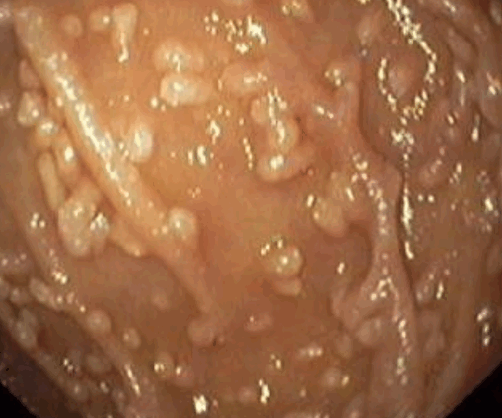

Рис. 18–9. Лимфоидная гиперплазия. Гранулированная слизистая оболочка содержит гиперпластические лимфоидные фолликулы.

Эндоскопическая картина каждого отдельного очага поражения такова: узелок сферической формы, с гладкой поверхностью, покрытый интактной или гиперемированной слизистой оболочкой (Рис. 18–9). Центральное пуповидное втяжение на поверхности мелкого образования можно обнаружить при ирригоскопии в виде пятнышка бария или непосредственно визуализировать при эндоскопии. Узелки локализуются на фоне интактной слизистой. Диагноз легко поставить на основании получения лимфоидной ткани при биопсии.

1) Эндоскопический ― выявление узелков различных размеров (2-10 мм, в среднем 5 мм) на слизистой оболочке желудка, тонкой кишки, толстой/прямой кишки. Такие узелки (чаще всего в виде выступающих папул) могут быть обнаружены при гастроскопии (ЭГДС), колоноскопии, энтероскопии или капсульной эндоскопии.

На фото ― НЛГ в 12-перстной кишке.

2) Гистологический метод ― выявление в слизистой оболочке и в поверхностной части подслизистого слоя увеличенных (гиперплазированных) лимфоидных фолликулов, которые обычно формируют группы, и могут практически сливаться между собой.